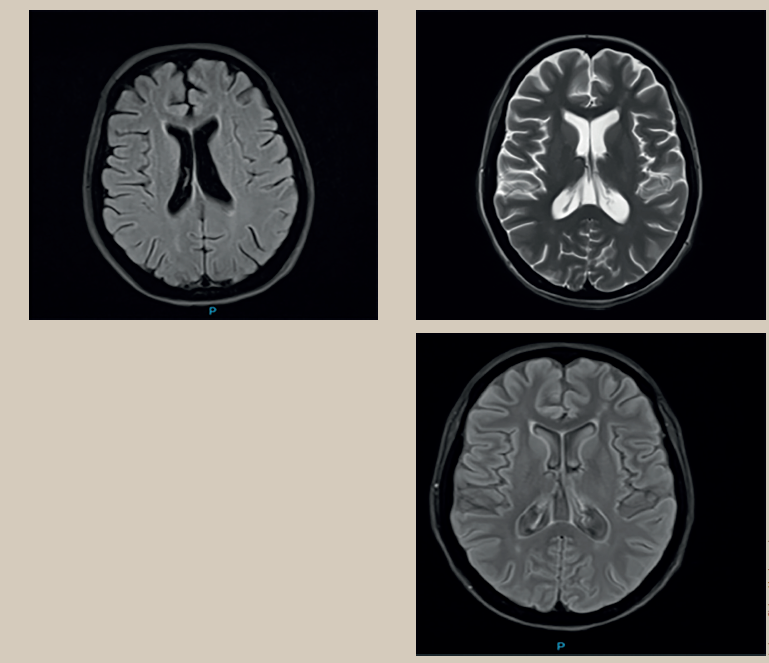

La resonancia magnética del cerebro había mos trado surcos y cisuras con aumento de su profundidad de forma generalizada. Sistema ventricular supratentorial con aumento de sus dimensiones. Presencia de múltiples hiperintensidades puntiformes subcorticales y periventriculares en secuencia T2 y FLAIR, localizado a nivel frontotemporoparietal bilateral, múltiples áreas de restricción puntiformes a nivel frontoparietal bilateral (figura1). A la administración de contraste se observó reforzamiento múltiple lineal a nivel temporooccipital derecho. Se realizó angiorresonancia de polígono de Willis y se observaron estructuras vasculares permeables, con disminución de su calibre a nivel de arteria cerebral media izquierda.

Figura 1 Resonancia magnética nuclear (RMN) contrastada de cerebro. Presencia de múltiples hiperintensidades puntiformes subcorticales y periventriculares a nivel frontoparietal bilateral en secuencia FLAIR comportándose algunas hiperintensas en secuencia de difusión, iso e hiperintensa marcada con la flecha en la imagen b y c.